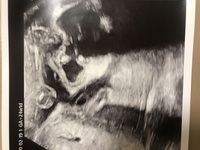

4Dエコー検査 Echo 4Dエコーでは、お腹の赤ちゃんの様子をリアルタイムで見ることが出来ます。 表情、あくび、指しゃぶり、まばたきしている様子や手足の動きなど、ママのお腹の中で赤ちゃんがどのように過ごしているかがわかります。あくびをする様子や、手を動かしているなどの仕草まで見ることができます。 3d/4dエコーのタイミング 3d/4dエコーのタイミングとしては妊娠週数15~32くらいが良いでしょう。それぞれ赤ちゃんの成長の度合いによって見え方が変わってきます。 妊娠15~19週#妊娠28週 の#3d4dエコー #あくび をしています。 ベビちゃんはお腹の中でもあくびをするんです しゃっくりだってします さすがにくしゃみはしませんけど 来月から1000円です 今月まで #無料ですよー 通常は診察券お持ちの方は5000円 診察券なしの方7000円です ️ 急いで〜藍

子宮内の異常、赤ちゃんの成長を確認するのに欠かせない検査となっています。 妊娠30週の時の双子の赤ちゃんの4Dエコーです。あくびをしたり、手で顔を隠したりする様子がわかりました! ブログはこちらから https娘と息子のエコー写真を比べてみました! エコー写真の性別判断は産まれてくるまでのお楽しみ 早くも妊娠5ヶ月で性別判明! ? 妊娠17週・18週のエコー写真 妊娠5ヶ月ごろだと、エコーでばっちりシンボルをみせてくれる男の子の赤ちゃんもいる頭殿長(座高)が42~43cm 体重は1300~1900gほど 子宮底長が256~296cmほど 赤ちゃんの表情はとても豊かになってきて、あくびやまばたき、指しゃぶりもよく見られます。 顔に手をあてて目を触ったりほほを触ったりすることもあるんですよ。 まだ生まれてくるには早すぎますが、万が一妊娠31週での出産(早産)になっても新生児治療の対象となる週数であり、胎児

妊娠週を過ぎると、赤ちゃんがあくびをしたり、指しゃぶりをしたり 人間らしい動きを観察できるため、感動されるママも多くいらっしゃいます。 当院でも「4dエコー」を導入しております。 2d、3dエコー写真につきましては、妊婦健診時に無料でお渡しをしております。129 Likes, 14 Comments AYAKO TAKEDA(tokuda) (@a_ko_pucci) on Instagram "胎動の幸せと ️ エコーであくび🥱してくれた奇跡的瞬間 ️ #胎動#胎動ムービー #妊婦検診 #29w4d #エコー動画 #エコーあくび#baby#マタニティ#妊婦" 155 Likes, 42 Comments @nohka_haruka on Instagram "里帰り前の最後の検診🤰 アクビがみれました💕👶 よく動くなーと思ってたらまた逆子😭 #4d#エコー#リアル#あくび #30週#30w4d#妊婦#赤ちゃん#里帰り#逆子"